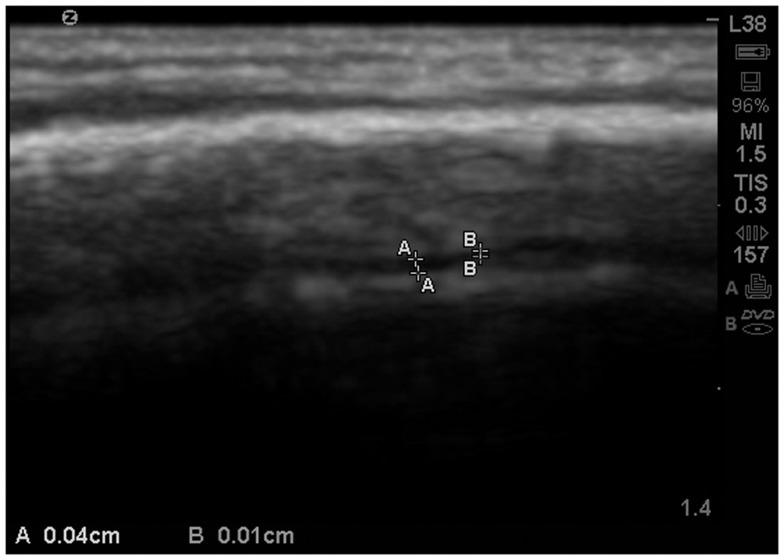

Comparisons of the extra-axial spaces indicated increases in the ASD subjects. For EAF we scored based on the gyral summit distances between the arachnoid membrane and the cortical pia layer (subarachnoid space): (1) <0.05 cm, (2) 0.05-0.07 cm, (3) 0.08-0.10 cm, (4) >0.10 cm. All of the neurotypical siblings scored 1, whereas the ASD mean score was 3.41 ± 0.67. We also defined cortical dysplasia as the following: hypoechoic lesions within the substance of the cortex, or disturbed layering within the gray matter. For cortical dysplasia we scored: (1) none observed, (2) rare hypoechogenic lesions and/or mildly atypical cortical layering patterns, (3) more common, but separated areas of cortical hypoechogenic lesions, (4) very common or confluent areas of cortical hypoechogenicity. Again all of the neurotypical siblings scored 1, while the ASD subjects' mean score was 2.79 ± 0.93.

对额外轴外空间的比较表明 ASD 受试者的空间增加。对于 EAF,我们根据蛛网膜膜和皮质软脑膜层之间的脑回峰距进行评分(亚蛛网膜空间):(1)<0.05cm,(2)0.05-0.07cm,(3)0.08-0.10cm,(4)>0.10cm。所有神经典型的兄弟姐妹均得分为 1,而 ASD 的平均得分为 3.41±0.67。我们还将皮质发育不良定义为以下情况:皮质实质内的低回声病变,或灰质内的分层紊乱。对于皮质发育不良,我们评分:(1)无观察到,(2)罕见的低回声病变和/或皮质分层模式轻度异常,(3)更常见,但皮质低回声病变分离区域,(4)皮质低回声性非常常见或融合区域。同样,所有神经典型的兄弟姐妹均得分为 1,而 ASD 受试者的平均得分为 2.79±0.93。